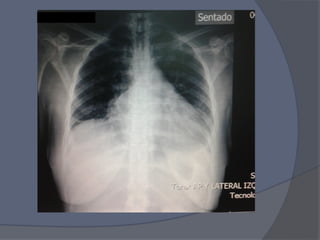

TAC AR

Aumento de

Grosor de

Pericardio

8mm

rodeando las 4

cavidades .

NO SG de

DERRAME

PERICARDICO

SIGNFICATIV

O

TAC AR Aumento de Grosorde Pericardio 8mm rodeando las 4 cavidades . NO SG de DERRAME PERICARDICO SIGNFICATIV O

Notas del editor

• #22 Aumento de Grosor de Pericardio , alcanza 8mm en zonas de mayor grosor , rodeando las 4 cavidades ; NO SG de DERRAME PERICARDICO SIGNFICATIVO 4 cavidades cardiacas bien Ao calibre normal, A pulmonar 30 mm diametro Adenopatias Para – Ao IZQUIERDAS la de mayor tamaño mas de 9 mm REDONDA 1 Bula Apical Resto de parenquima normal Atelectasia subsegmentaria ibsal Estructuras abdominales visibles normales Osteofitos en columna y Mineralizacion visible disminuida ( sugiere osteoporosis) , no Fracturas